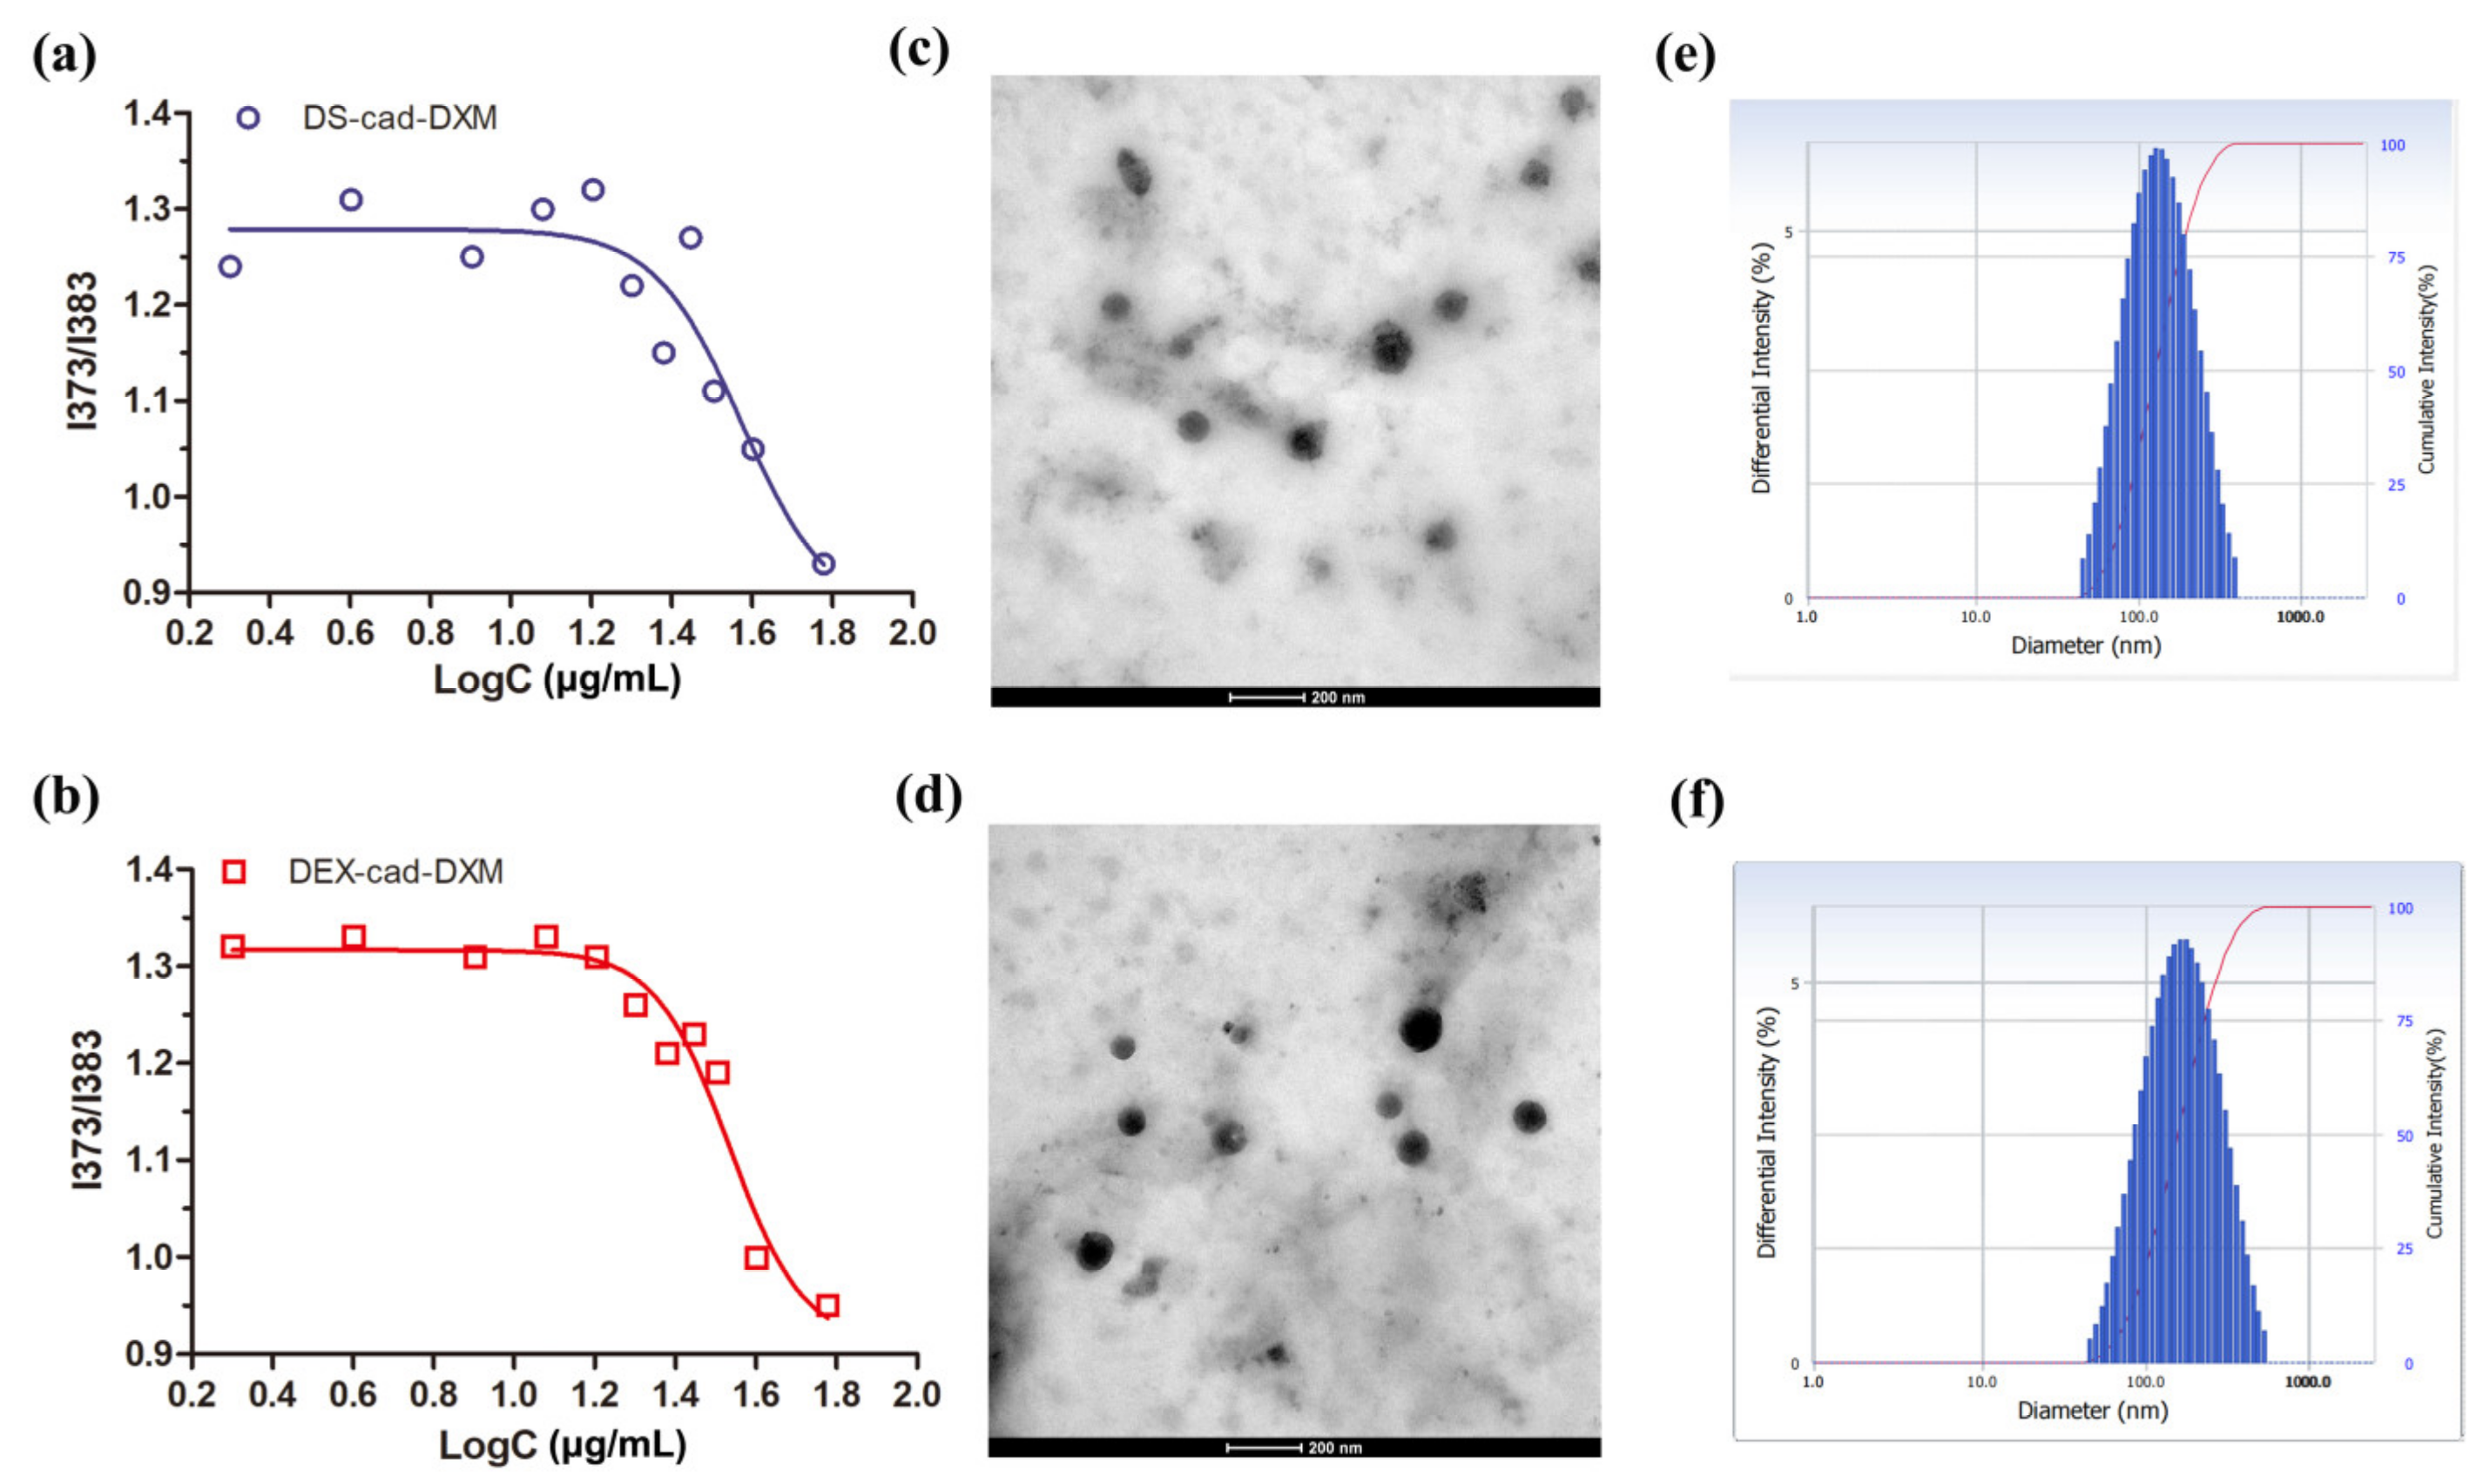

2.2. Preparation and Characterization of Micelles

| DXM-Loaded Micelles | Size (nm) | Zeta (mV) | PDI | DL (%) |

|---|---|---|---|---|

| DXM@DEX-cad-DXM | 147 ± 12.1 | −17.4 ± 1.8 | 0.209 ± 0.5 | 24.3 ± 3.7 |

| DXM@DS-cad-DXM | 136 ± 11.3 | −19.9 ± 2.1 | 0.214 ± 0.7 | 25.4 ± 3.9 |